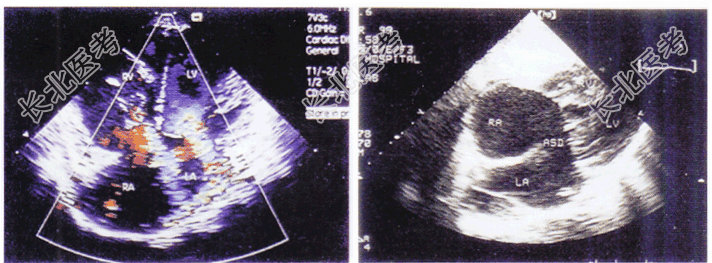

- 单项选择题如图,二维和彩色多普勒超声心动图所示, 该病例可考虑诊断为

A、二尖瓣、三尖瓣关闭不全

B、上腔型房间隔缺损

C、心内膜垫缺损部分型

D、Ⅱ型房间隔缺损

E、心内膜垫缺损完全型